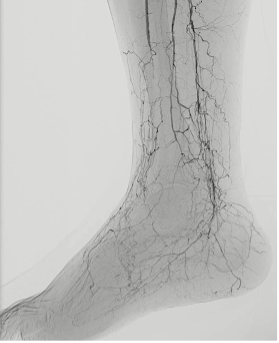

Approximately 20% of patients with CLTI patients fall into the "no-option" category, meaning they have no suitable arterial targets for revascularization due to diffuse or distal disease (Figure 1). These patients typically have a history of multiple failed revascularization procedures or present with anatomical limitations that preclude further surgical or endovascular intervention.4

Clinical outcomes in this group are poor. More than half face major amputation or death within 6 months of diagnosis. This grim prognosis underscores the urgency for alternative strategies capable of providing durable limb salvage. Chronic wounds and severely ischemic tissue that cannot be revascularized by standard means typically do not heal, leading to escalating complications and diminished quality of life (Figure 2).